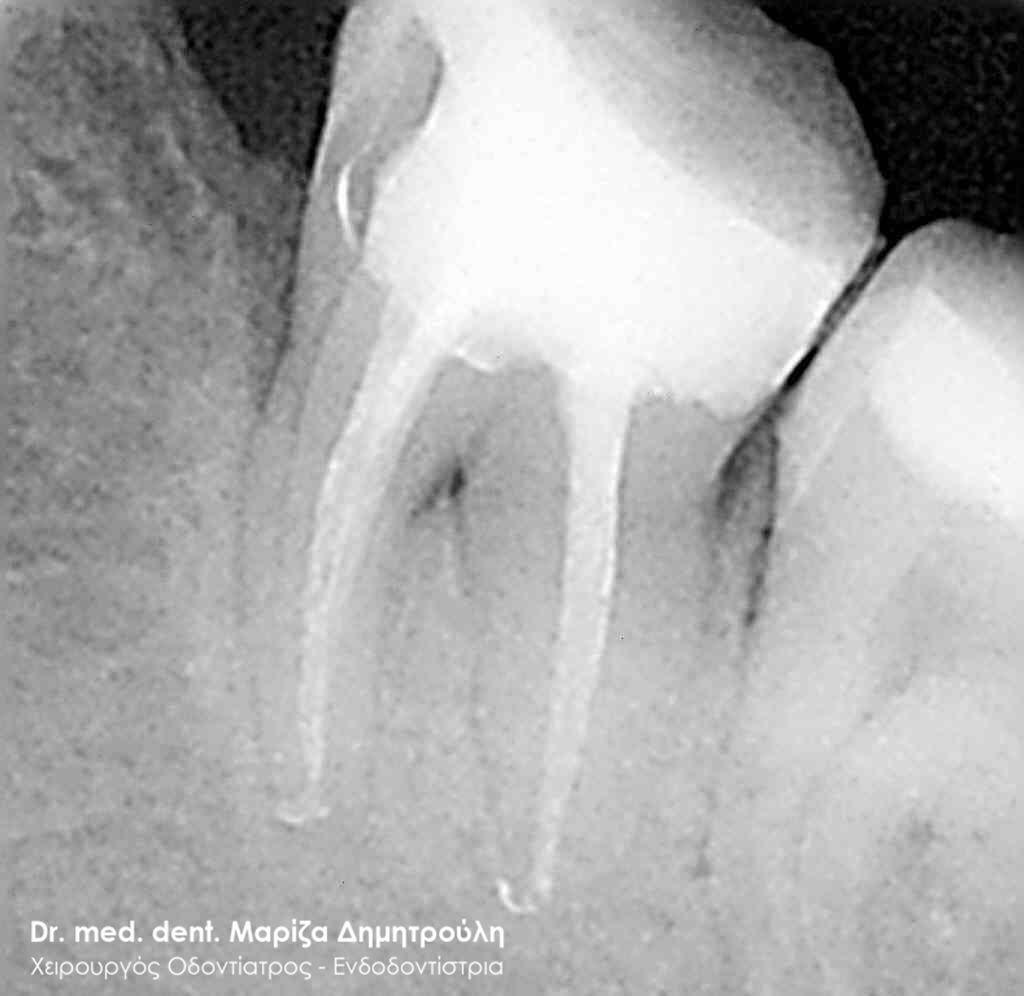

Οι φωτογραφίες δείχνουν τους ριζικούς σωλήνες του δοντιού πριν (αριστερή φωτογραφία) και μετά (δεξιά φωτογραφία) την επεξεργασία του δοντιού με μηχανοκίνητα εργαλεία.

ΠΡΙΝ

ΜΕΤΑ

Η ασθενής παρουσιάστηκε στο ιατρείο με έντονο πόνο στην αριστερή μεριά της πάνω γνάθου. Μετά την κλινική και ακτινογραφική εξέταση διαπιστώθηκε οτι ο πρώτος γομφίος ήταν τερηδονισμένος σε μεγάλη έκταση και βάθος. Η ακτινογραφία αποκάλυψε επίσης μία ακρορριζική αλλοίωση σε 2 από τις 3 ρίζες του δοντιού.

Για τη θεραπεία του δοντιού ήταν απαραίτητη η απονεύρωσή του.

Η θεραπεία ξεκίνησε με τη διάνοιξη του δοντιού, τη χημικομηχανική επεξεργασία του με μηχανοκίνητα εργαλεία και την τοποθέτηση φαρμάκου μέσα στους ριζικούς σωλήνες του δοντιού. Στην επόμενη κιόλας συνεδρία η ασθενής είχε ανακουφιστεί από τα συμπτώματα πόνου.

Εφόσον το δόντι ήταν ασυμπτωματικό η διαδικασία της απονεύρωσης ολοκληρώθηκε με την έμφραξη της ρίζας του δοντιού με ειδικό εμφρακτικό υλικό.

Η θεραπεία της απονεύρωσης ολοκληρώθηκε σε 3 ραντεβού.

Στην δεξιά ακτινογραφία φαίνεται οτι η ακρορριζική αλλοίωση σε μία από τις ρίζες του δοντιού είχε κιόλας υποχωρήσει σε μικρό χρονικό διάστημα από την έναρξη της απονεύρωσης του δοντιού.